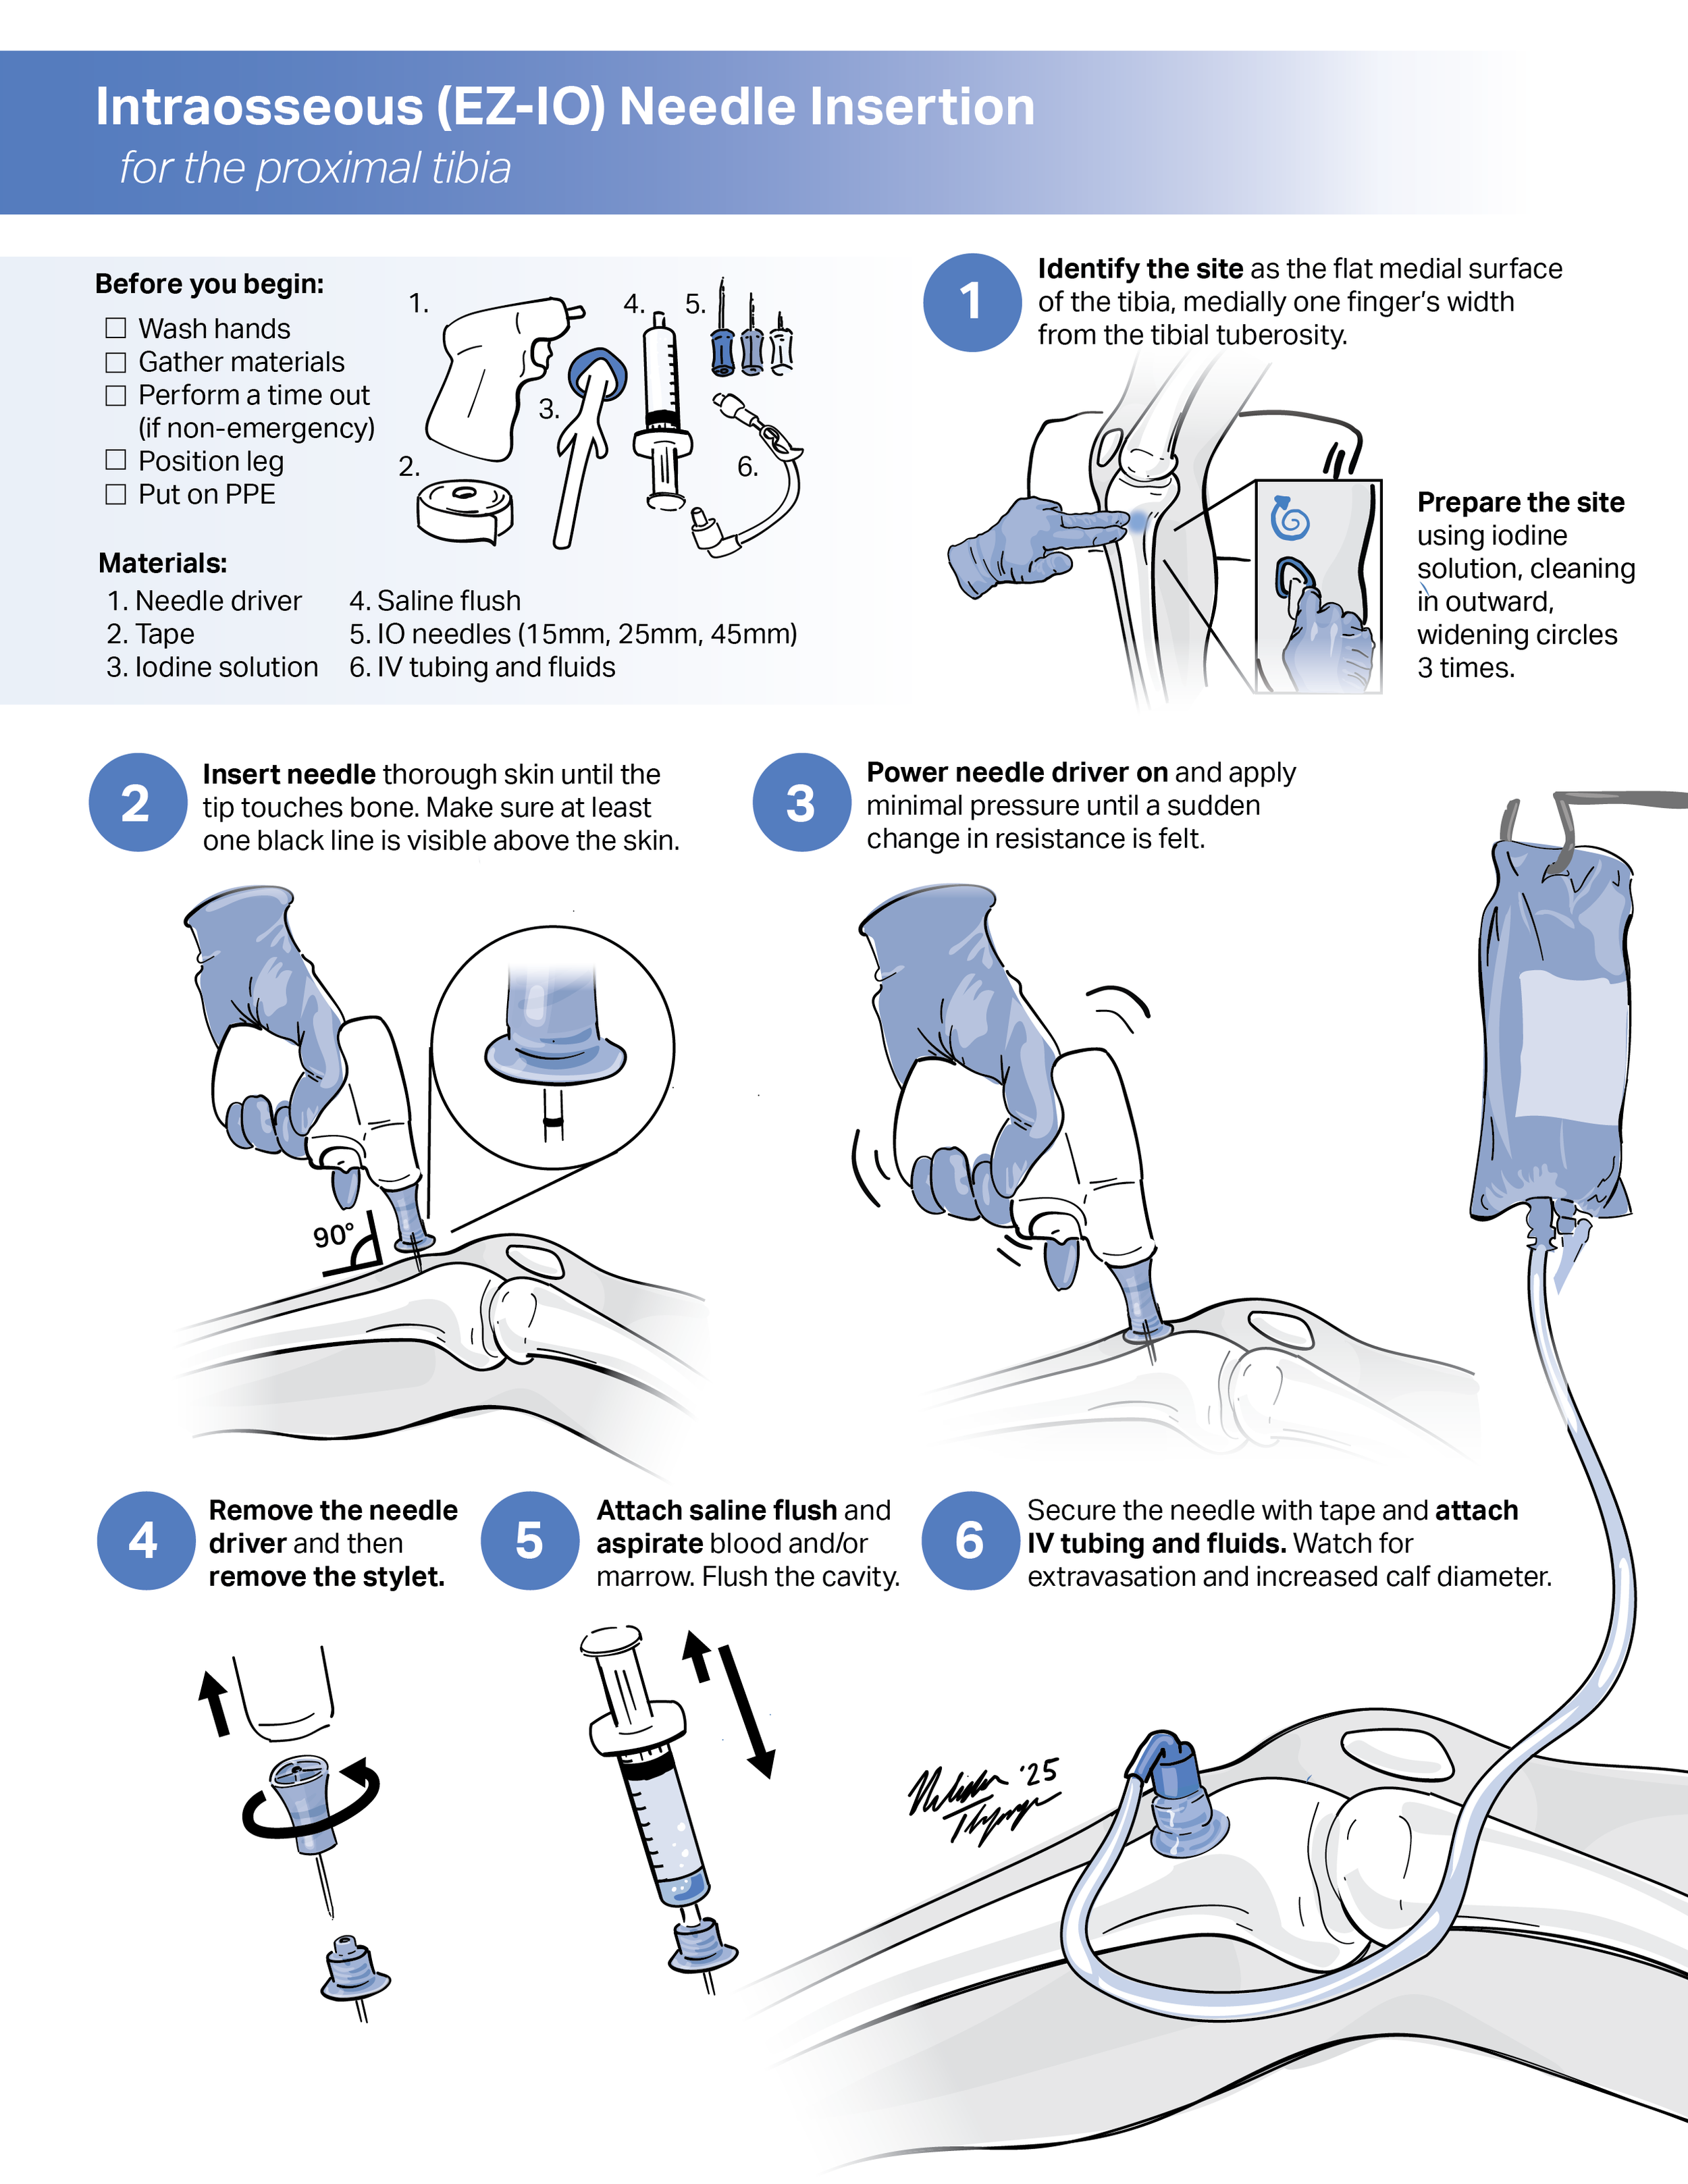

Instructional handout: Intraosseous (EZ-IO) Needle Insertion